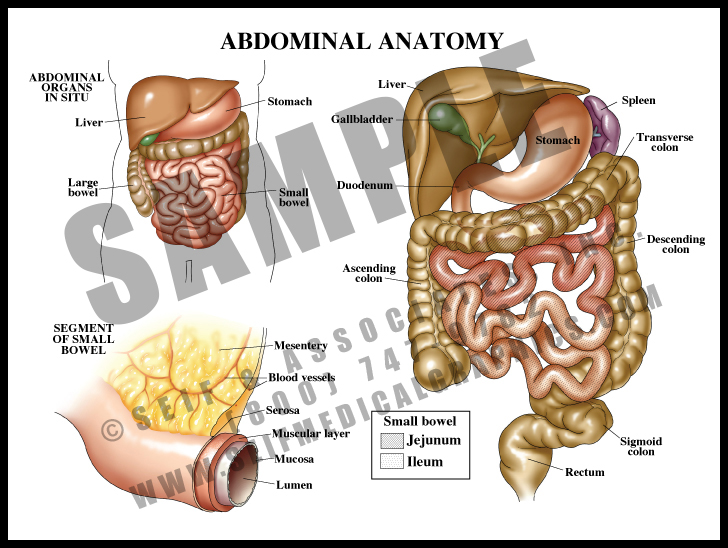

Diagram Of The Abdominal Organs

guidelibmisjoinder.z22.web.core.windows.netUnderstanding Abdominal Divisions | Anatomy Snippets | Complete Anatomy

guidelibmisjoinder.z22.web.core.windows.netUnderstanding Abdominal Divisions | Anatomy Snippets | Complete Anatomy

completeanatomy.cnAbdomen (Human Anatomy) - Image, Definition, Function, Diseases And More

Abdominal Anatomy Medical Illustration Medivisuals

medivisuals1.comanatomy abdominal 01a illustration medical medivisuals1

medivisuals1.comanatomy abdominal 01a illustration medical medivisuals1

Abdominal Anatomy, Illustration - Stock Image - F029/5259 - Science

www.sciencephoto.comabdominal

www.sciencephoto.comabdominal

Abdominal Anatomy, Illustration – Bild Kaufen – 13199974 Science Photo

www.science-photo.deAbdominal Anatomy - S&A Medical Graphics

www.science-photo.deAbdominal Anatomy - S&A Medical Graphics

samedicalgraphics.comanatomy abdominal medical illustration

samedicalgraphics.comanatomy abdominal medical illustration